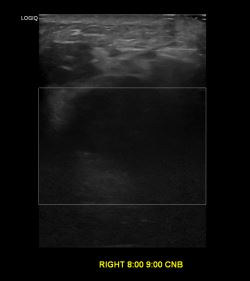

상기환자 외부검사이상으로 정밀검사위해 내원하신 40대 여성분으로

우측유방 혹 총조직검사 시행해 유방암 진단되었습니다